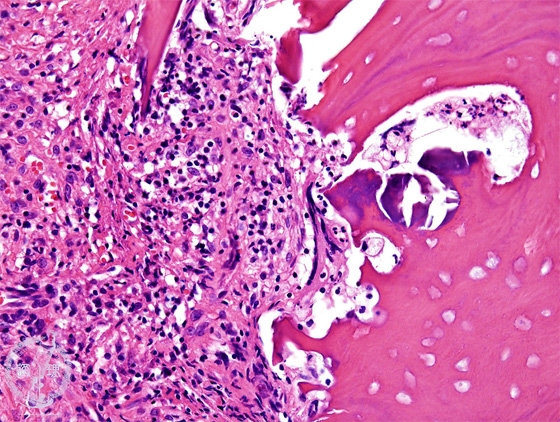

- (5)Suppurative osteomyelitis

Microscopic view (HE: high power view):Infiltration of neutrophils and fibrosis are seen. Bone is necrotic, with disappearance of the nuclei within the lacuna of the bone.